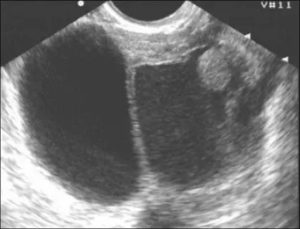

Подтвердить диагноз могут только методы эндоскопии – при них визуально видно газовые пузырьки по ходу кишки.

Могут быть также использованы методы рентгенологической диагностики с контрастом или без него.

Диагностика включает исследование полости кишечника (эндоскопические методы), состояние органов эпигастрии (узи, рентген с контрастированием), анализы мочи, крови и кала.